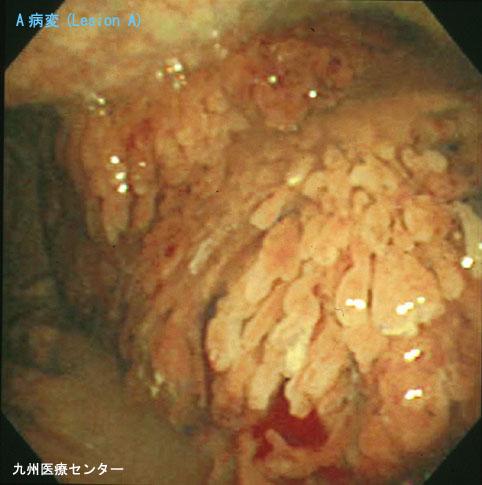

A case of villous tumor of the stomach with diodenal adenoma.

Fukuoka Pref., National Hospital Organization Kyushu Medical Center

Location

Stomach/Body

Technique, Method

Endoscopy

Macroscopic Types

Type 0/Others

Size

40 -

Depth of Tumor Invasion

mucosa